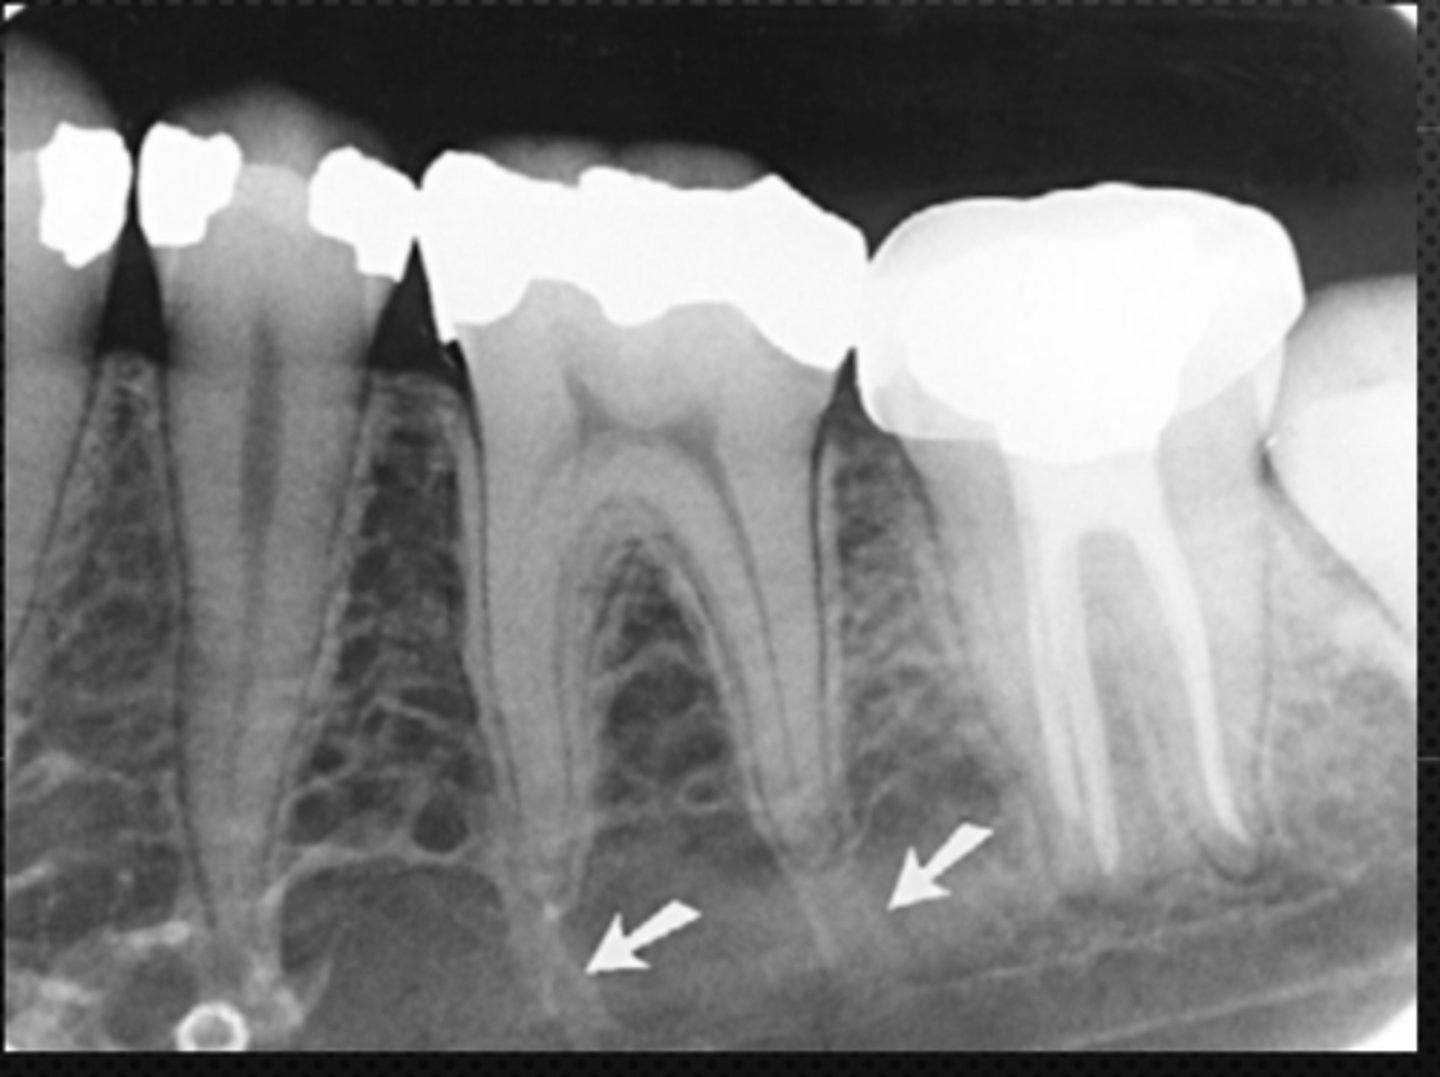

Mandibular canal

Identify the structure

<p>Identify the structure</p>

Identify the radiolucent structure

<p>Identify the radiolucent structure</p>

Nutrient canals (neurovascular canals)

What is causing the thick radiolucent line surrounding the dotted line?

<p>What is causing the thick radiolucent line surrounding the dotted line?</p>